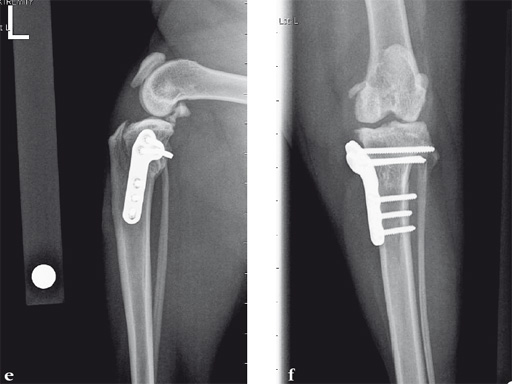

Case 2: Cat

(Case provided by Brian Beale, Houston, USA)

A 10-year-old female, spayed, 6.0 kg cat had a partial tear of the left cranial cruciate ligament, meniscal mineralization, and a medial meniscal tear. The cat was treated with a partial meniscectomy and TPLO . A 2.0 mm TPLO plate was perfect for this cat due to the slope of the tibial plateau (25) and the size of the cat. Three 2.0 mm locking screws were used proximally and three 2.0 mm cortex screws were used distally. The contour of this plate does not perfectly match the contour of the proximal tibia, but use of locking screws in this segment avoids any potential angulation of the segments as the screws are tightened. The cat healed uneventfully and returned to normal function.